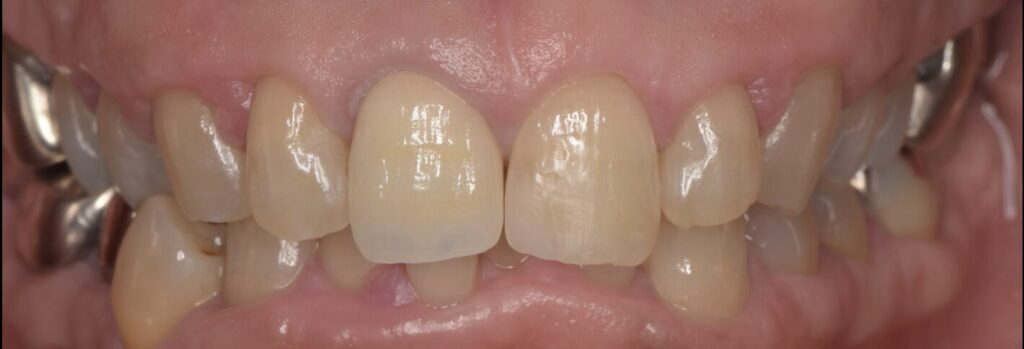

前歯のセラミッククラウンで治療した症例

Before

| 治療内容 | セラミッククラウン |

| 治療期間・治療回数 | 根管治療2回、セラミッククラウン2回 |

| 治療費用 | 170500円(税込) |